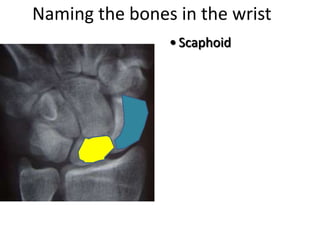

This document provides an overview of hand anatomy including:

- Naming the bones, joints, tendons, nerves and skin landmarks of the hand and wrist.